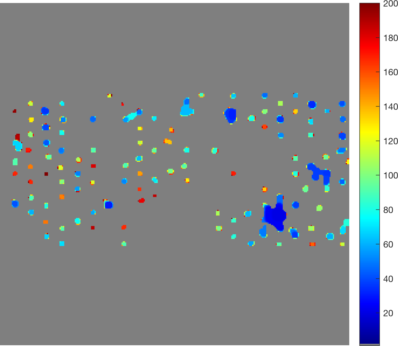

In Figure 14 (a), (d), (g) and (j) experimental data sets are shown. From the original image sets, consisting of three different fluorescent color channels, we extracted the tumor cell marker (green) and used those images as input for our multiscale segmentation approach. Although the difficulties vary between all images (inhomogeneous background, noise, cell clusters, mixture of size and intensity scales), we can process all images with our multiscale segmentation approach with the exact same parameters. This is essential for the development of a user-friendly (parameter-free) toolbox for CTC analysis. Note that the dim spots in image (d) are not cells but only pores of a filter used to collect cells (bright spots) and therefore it is not desired to segment them. The resulting spectral response functions for all four images are shown in Figure 14 (b), (e), (h) and (k) with a color coding corresponding to the coding used in the segmentation results in (c), (f), (i) and (l). The color coding of the response function shows that all objects which appear later in our segmentation and therefore belong to finer scales have a yellow to reddish color in the color-coded segmentation. The very large and intact cells are blue (with some small artifacts at the boundary) and smaller cells (or large fragments) are shown in light blue to green. We can nicely observe that the object colors cover the whole color scale range. For images that are more complex (e.g. (d) and (j)) also the spectral response function is more complex but the color-coded segmentation shows that nearly every object appears in one step and thereby has a clearly defined scale that we use as a feature in our classification approach. Here, we profit from the fact that not only Wulff shapes (perfectly circular objects) but also other eigenshapes appear in one step in our segmentation. Hence, this segmentation approach not only provides all contours automatically without any parameter adaptations but simultaneously also a simple classification of cells based on their size (scale resp. color/appearance time). This analysis can be applied to all color channels separately and be used together with more features in a subsequent automatic classification approach. The constants and can again simply be estimated a-priori from the data by a simple thresholding and averaging approach and are fixed throughout the iterative process.